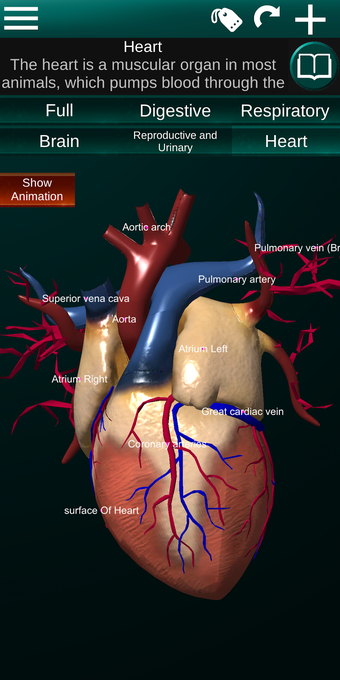

Diese Anwendung zeigt ein dreidimensionales Modell der menschlichen Körperorgane und eine Beschreibung aller von ihnen.

Sie können jedes Organ wie Herz, Gehirn, Lunge, Fortpflanzungssystem, Leber, Darm, Eierstock, Hoden, Magen, Niere usw. anfassen.

Sie können die App verwenden, um herauszufinden, welches die verschiedenen Körperorgane sind und welche Funktionen sie haben.